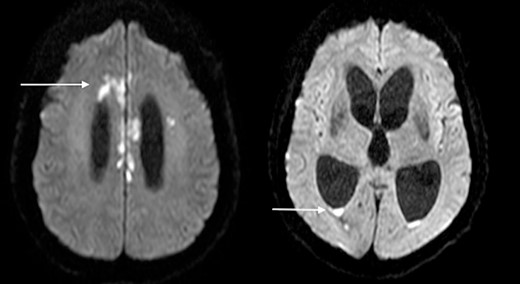

The patient became progressively obtunded, requiring intubation and ventilation in the Intensive Care Unit. Bacterial culture results demonstrated colonization with multiple microorganisms including Staphylococcus aureus, Candida albicans, Proteus mirabilis, Klebsiella pneumoniae, Serratia marcescens, and Lactobacillus species. This prompted the modification of antimicrobial coverage to Ceftazidime-Avabactam, Daptomycin, Metronidazole, and Vancomycin. Repeat imaging 10 days after presentation showed progression to diffuse cerebritis and pyogenic ventriculitis (Fig. 4). A multidisciplinary meeting was held with the patient’s next-of-kin and the decision was to provide comfort measures in light of the overall clinical picture, progression of infection, and existing poor patient performance status. The patient passed away peacefully in the presence of his family 13 days following his admission.

Diffusion-weighted MRI-brain showing intensely high signal in cerebral cortex (arrow) and ventricles (arrow) consistent with infective cerebritis and ventriculitis.